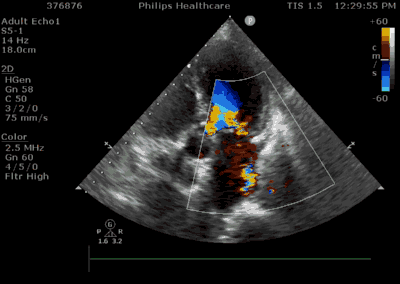

3月30日患者先在全麻下进行TEE(经食道超声心动图)再次评估瓣膜情况(视频4、视频5、视频6 ),确定为二尖瓣前组乳头肌断裂致二尖瓣前瓣脱垂并重度返流,其脱垂部位、瓣叶结构、瓣口面积等适合进行二尖瓣夹合术。术中IABP辅助,ECMO湿备,穿刺右侧股静脉,在TEE指导下顺利穿刺房间隔,随后送入二尖瓣夹合系统,在超声指导下于二尖瓣A2/P2区植入一枚Mitraclip XTR夹合器(视频7),术后TEE评估返流程度从5+降至1+(视频8 ),夹合结果满意,二尖瓣呈双孔启闭(视频9 ),术后二尖瓣平均跨瓣压差1mmHg(图1),收缩期肺静脉返流消失(图2 ),手术总耗时80min。香港亚洲医疗中心林逸贤教授通过视频连线进行手术全程技术支持。

图2